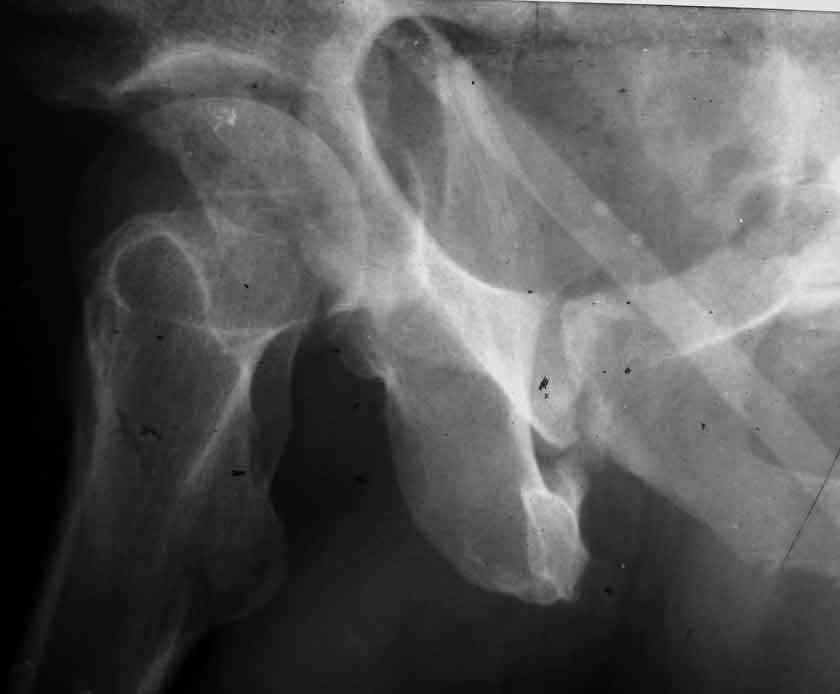

I am sending another iliac view, and a marked version of the AP I already sent. In this AP, the

proximal part of the greater sciatic notch as well as the distal parts of the ilioischial and iliopubic lines are marked with a grey interrupted line. A white interrupted line marks what could be an exit through the obturator foramen, or so I assume.